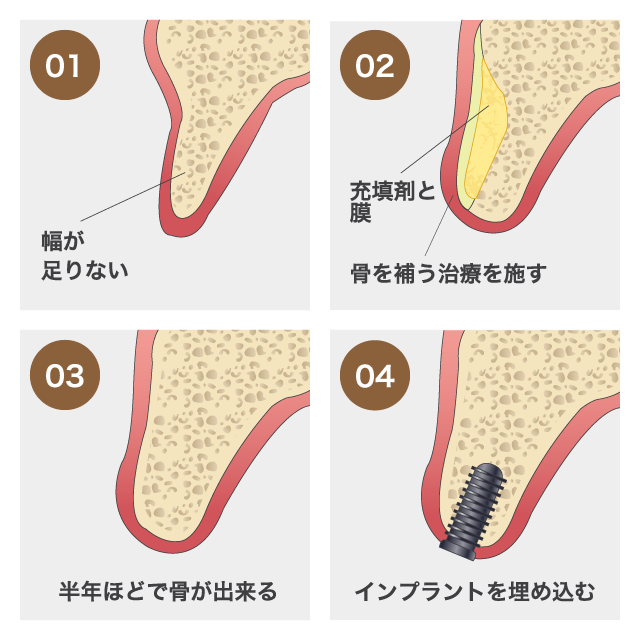

インプラント治療とは術前診査・診断を十分に行った上で、歯が抜けてしまった部分にインプラント(人工歯根)を埋め込み、その上から自然な見た目の人工歯を装着させるという治療法で、骨にしっかりとインプラント(人工歯)を定着させるため、自分の歯のようにしっかり、思い切り噛めるようになります。